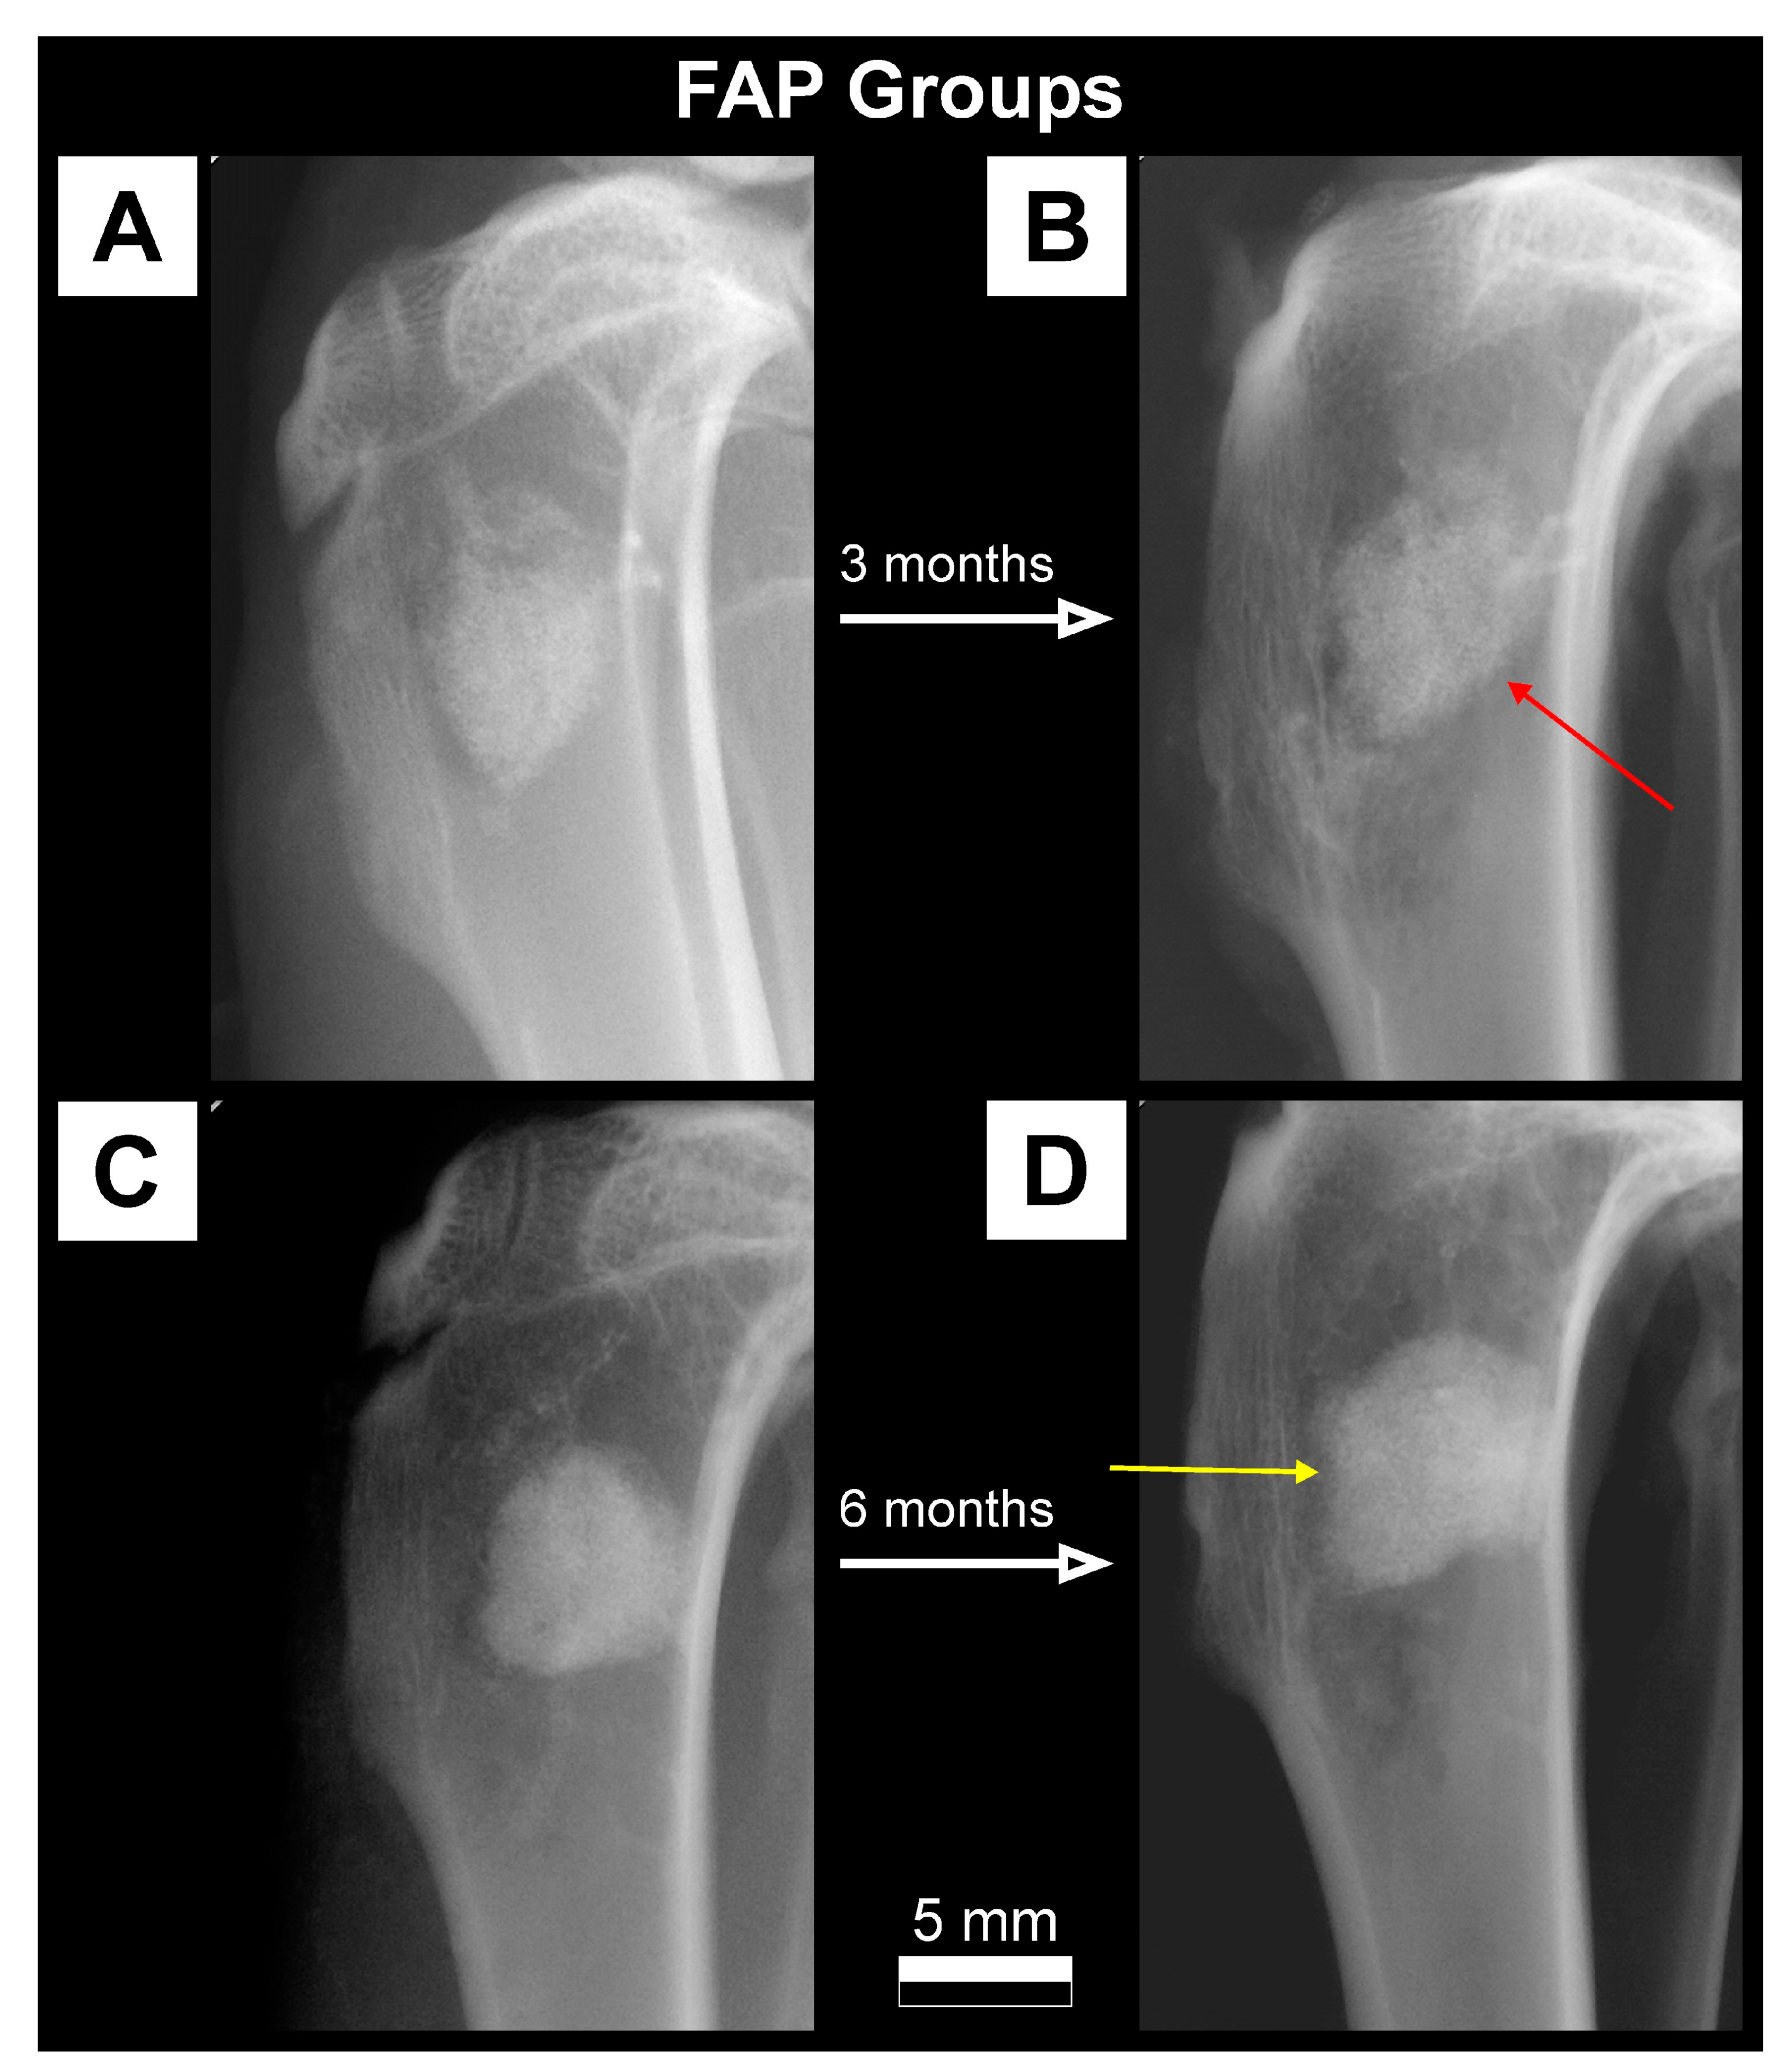

2.3.1. X-ray Imaging—Conventional Radiography

3.1. Qualitative Analysis of Bone Substitute Materials

3.2. Quantitative Analysis of Bone Substitute Materials